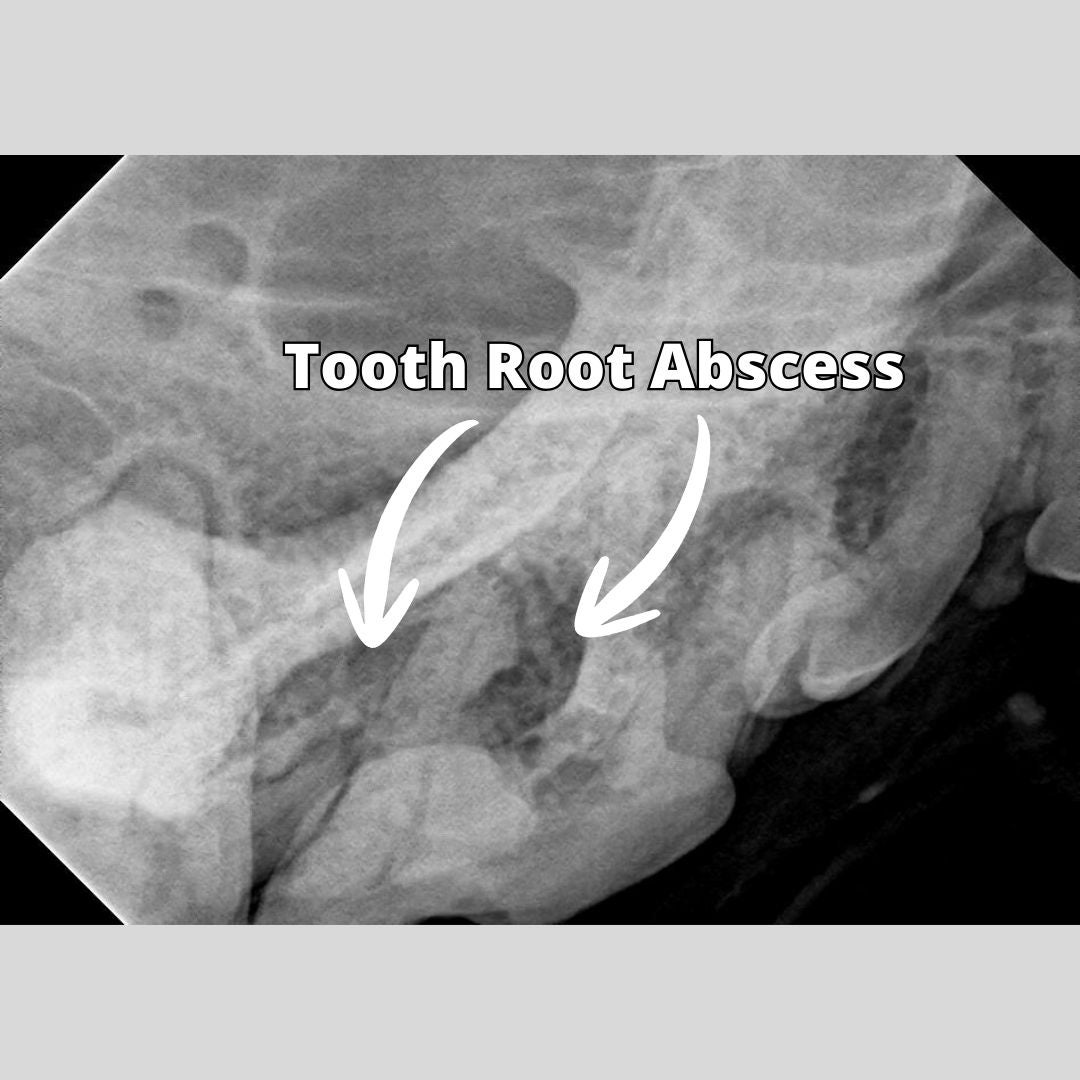

I recommended scheduling a complete oral health assessment and treatment, also known as COHAT, which is a full dentistry with dental xrays, scaling, and polishing of the teeth. The dental xrays would tell me if in fact the tooth was abscessed. Ruby returned the following week for her procedure. I induced general anesthesia and took full mouth dental xrays. Sure enough, the tooth was infected. This particular tooth has 3 roots and 2 of the roots had what is called a periapical lucency indicating bone loss and infection at the root tip. The tooth needed to be extracted. After getting the owner's permission, I performed an extraction of the tooth. This entails making an incision into the gum, elevating a gingival flap, dividing the tooth into 3 parts, elevating and removing each root intact, flushing the socket, and then closing the gum tissue over with absorbable sutures.